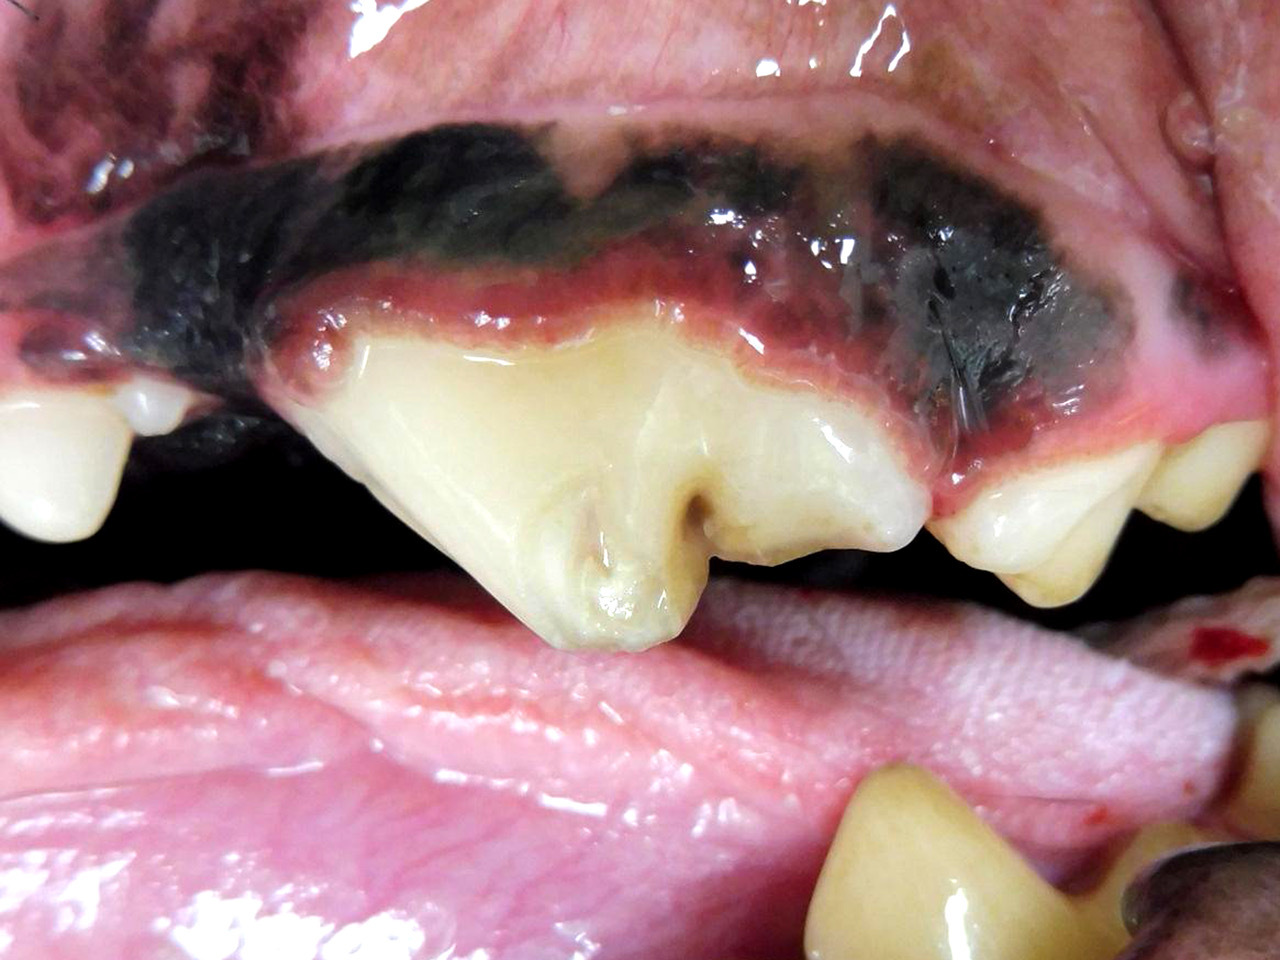

Zwei Wochen später ist es soweit: Mia wird zur Zahnstatuserhebung und Versorgung der Zahnfraktur in der Tierklinik vorgestellt. Nachdem sie in Frauchens Armen friedlich einschläft geht es in den Zahn-OP. Zuerst werden die Zähne mittels Ultraschall von Zahnstein und Plaque befreit. Im Anschluss werden - wie auch bei uns beim Zahnarzt - alle Zähne sondiert und geröntgt. Fast 30% aller klinisch wichtigen Befunde sind bei Hunden nur auf Dentalröntgen zu erkennen; bei der Katze sind es sogar noch mehr. Nur so kann der Tierarzt die Narkose ausreichend nutzen um alle für das Tier schmerzhaften Probleme zu behandeln.

Bei Mia gibt es außer der bekannten Zahnfraktur des linken Oberkieferreißzahns (Prämolarer 4) keine Auffälligkeiten. Bei der Sondierung und Betrachtung der Bruchkante mit der Lupenbrille zeigt sich, dass noch eine ganz feine Schicht Zahnsubstanz (Dentin) Mias Wurzelkanal bedeckt. Das Dentin bietet zwar noch einen gewissen Schutz, im Gegensatz zum Zahnschmelz (der beim gesunden Zahn die äußerste Schicht der Zahnkrone bildet) hat es jedoch feine Kanälchen durch die Bakterien eindringen könnten. Im Röntgenbild zeigt sich bisher kein Hinweis für eine bestehende Infektion, und zusammen mit der Besitzerin wird entschieden, dass Mia den Zahn erstmal behalten darf, aber in sechs Monaten erneut zur Zahnröntgenkontrolle kommen muss. Da die feine Dentinschicht über dem Wurzelkanal weder vor Infektionen noch vor Umwelteinflüssen schützt, wird die Bruchkante mit dem Bohrer geglättet und der Zahn mit Kunststoff versiegelt.